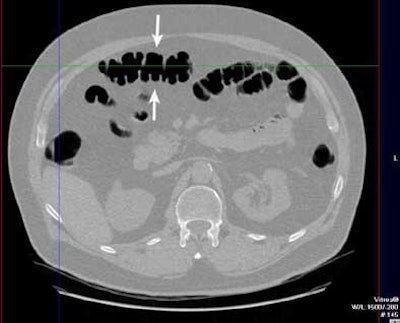

| A 6- to 9-mm adenoma in the ascending colon was missed due to perceptual error. Above supine axial image through the ascending colon. The arrow points to a 6- to 9-mm polyp, which was not seen on the initial interpretation. Below, 3D endoluminal view shows the polyp (arrow) on a fold. Images courtesy of Dr. Eric Paulson. |

Ten of the 13 perceptual errors were "flat-out misses" in which the lesion could be seen in retrospect, Paulson said. Eight of the 13 were polyps located on a haustral fold. In nine of the 13, the polyp could be seen on one view -- prone or supine -- but not the other view, due to residual fluid or a collapsed bowel segment. And there were two missed sigmoid adenomas in the setting of impressive sigmoid diverticulosis that may have contributed to the misses, he said.